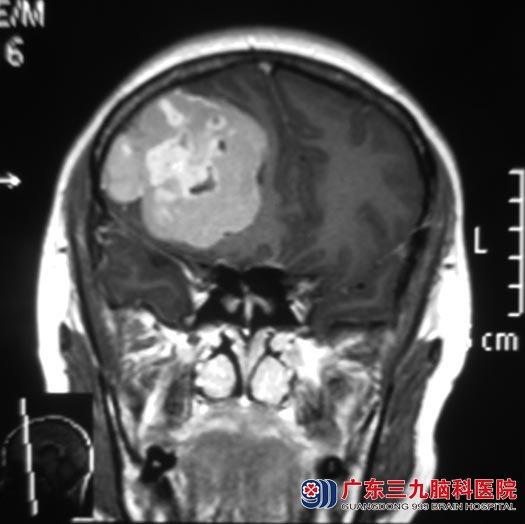

涂女士八天前出现右侧头顶部蚂蚁搔爬般痛,伴恶心呕吐,休息无好转。当地医院头颅CT检查提示右侧额颞叶占位性病变,性质待查。广东三九脑科医院头颅MR检查:右侧额部示不规则块状占位性病变,大小约6.0cm×4.5cm×6.5cm。

▲手术前MR